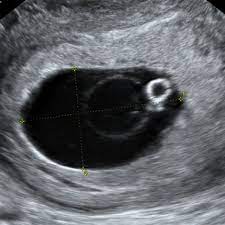

La ecografía transvaginal se usa comúnmente para establecer con precisión la edad gestacional y confirmar la ubicación del embarazo.

Un saco gestacional visto como una pequeña colección de líquido anecoico dentro de la cavidad endometrial, es la primera evidencia ecográfica del embarazo.

El saco gestacional se puede ver con ecografía transvaginal a las 4 o 5 semanas de gestación.

El saco vitelino, se observa en la ecografía como un anillo de gran resonancia ecogénica con un centro anecoico, dentro del saco gestacional, y normalmente se puede ver hacia la mitad de la quinta semana de gestación.